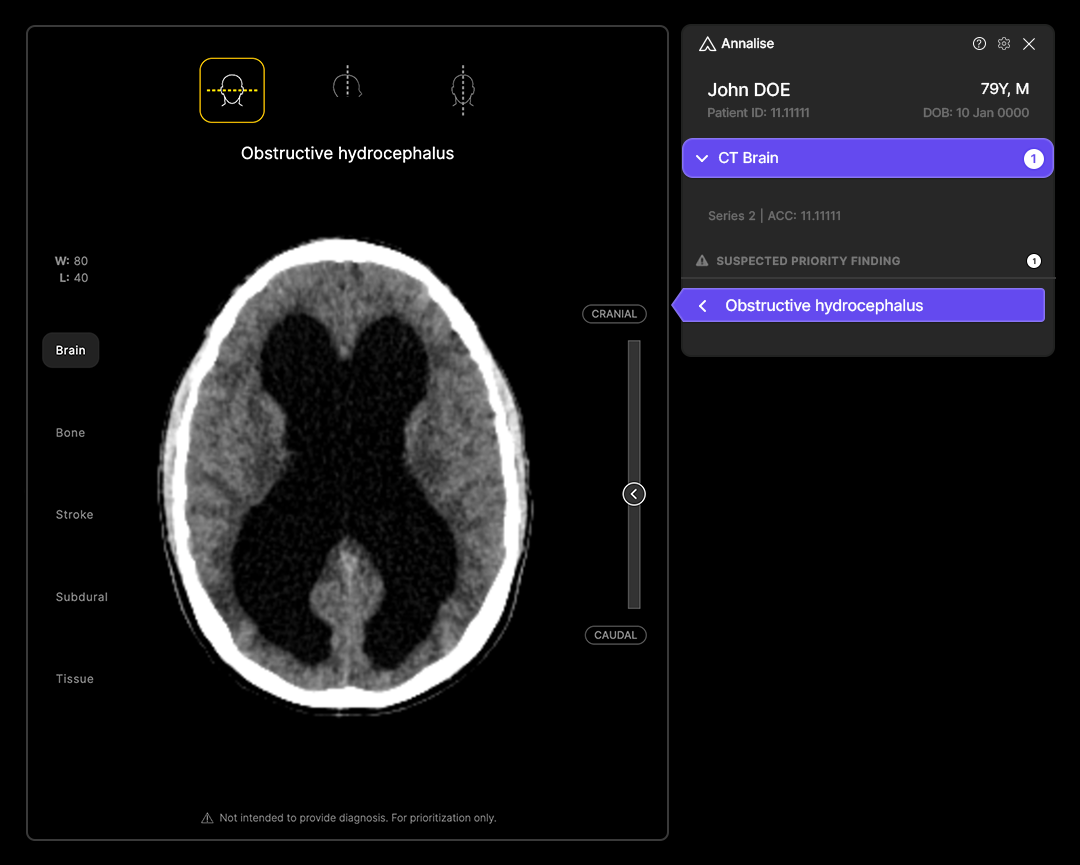

New York, 2nd August, 2024 – Leading radiology AI provider Annalise.ai has announced that it has secured a Medicare New Technology Add-on Payment (NTAP) from the Centers for Medicare & Medicaid Services (CMS) for the use of Annalise – Obstructive Hydrocephalus, part of the Annalise Critical Care AI solution, to triage non-contrast brain CT scans suspected of obstructive hydrocephalus (OH). In approving the payment, CMS recognized the device’s substantial clinical improvement over existing services, consistent with a Breakthrough Device Designation awarded to the technology by the Food and Drug Administration.

Annalise.ai’s solution is now the only radiology AI triage device in the US eligible for separate, additional Medicare hospital payment. This innovation triages non-contrast brain CT scans suspected of obstructive hydrocephalus (OH). Obstructive hydrocephalus is a life-threatening condition involving the build-up of cerebrospinal fluid (CSF) in the brain and can be fatal if not detected and treated urgently.

The Annalise.ai solution addresses these challenges by identifying non-contrast brain CTs with findings suggestive of obstructive hydrocephalus within minutes of the scan. It flags these cases in the radiologist’s worklist and alerts managing clinicians, supporting faster diagnosis and treatment. The solution demonstrates excellent performance with an AUC of 0.987, and sensitivity and specificity up to 97.5% and 95.3% respectively1.

Obstructive hydrocephalus is one of 12 FDA-cleared urgent findings that comprise Annalise Critical Care AI, the most comprehensive AI triage solution for chest X-ray and non-contrast head CT available in the US2.